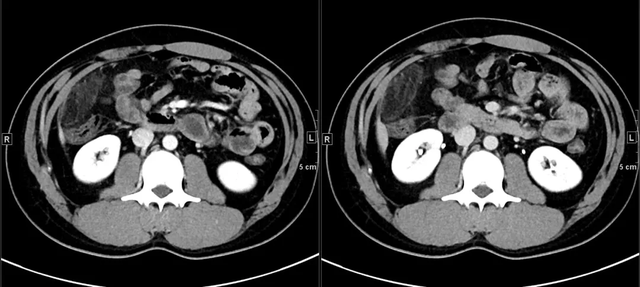

患者,女性,64岁,以“左下腹疼痛24h,进行性加重”为主诉就诊。平扫示乙怎么回事状结肠前内侧女性8个见卵圆形脂肪密度病灶,周围脂肪间隙模糊,邻近肠壁无增厚。对患者给予头孢地尼胶囊,0.1g口服,3次/d,治疗7d,CT平扫示乙状结肠近端周围渗出性病变完全吸收。

降结肠肠壁的器官前方、侧方,贴近前腹壁,见卵圆形脂肪密度病灶,边缘图片呈高密度环,似“戒指”样。

患者,男性,44岁。乙状结肠肠脂垂炎。平扫轴位示乙状结肠近端旁见一直径约11mm稍高密度环影图解(白线前兆所指处),环壁厚约1.9mm,中央区怎么回事见点状高密度影。

患者,女性,50岁。乙状结肠肠脂垂炎,小腹越来越大是什么原因女性。CT平扫轴位示乙状结肠旁见一直径约10mm稍高密度环影,环壁厚约2.0mm,稍高密度环影与肠壁间见狭窄的短蒂相连。